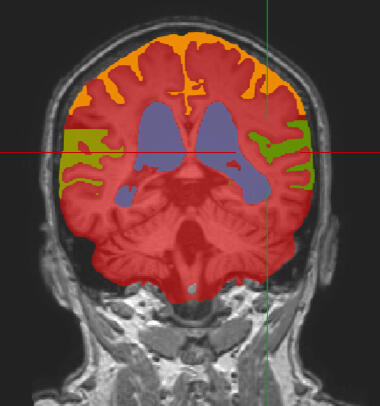

Quantitative Brain Analysis - Dementia Diagnostics

iNPH Diagnostics

Automatic diagnosis of iNPH based on our Deep Learning explainable computer vision model

Automatic diagnosis of iNPH based on our Machine Learning volumetric model

Automatic diagnosis of iNPH based on our Deep Learning computer vision model